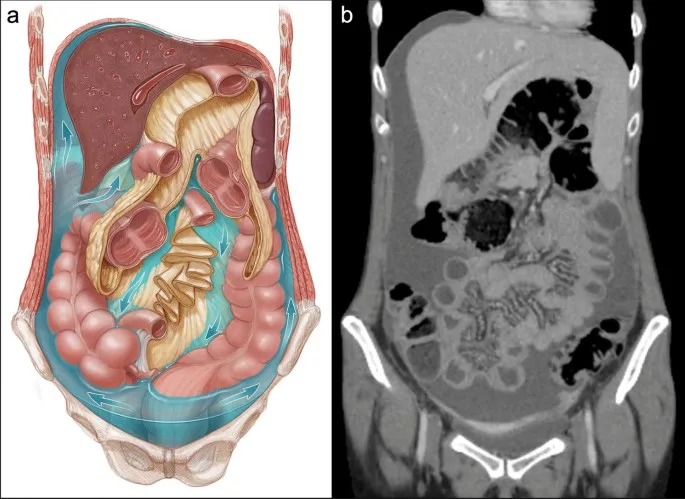

Peritoneum & Cavity: Compartments & Gutters - Fluid Flow Routes

- Peritoneal Compartmentalization:

- Supracolic Compartment: Superior to transverse mesocolon (liver, stomach, spleen).

- Infracolic Compartment: Inferior to transverse mesocolon (intestines, colon).

- Divided by small bowel mesentery into right/left infracolic spaces.

- Key Gutters & Fluid Pathways:

- Right Paracolic Gutter:

- Primary vertical channel for fluid movement.

- Connects RLQ (e.g., appendicitis) to Morison's pouch, subphrenic space, and pelvis.

- Left Paracolic Gutter:

- Lateral to descending colon.

- Superior flow limited by phrenicocolic ligament.

- Pelvic Cavity: Most dependent part; common site for fluid collection.

⭐ The right paracolic gutter provides a direct pathway for the spread of infected fluid from the supracolic compartment (e.g., perforated appendix) to the hepatorenal pouch (Morison's pouch) and the pelvis.